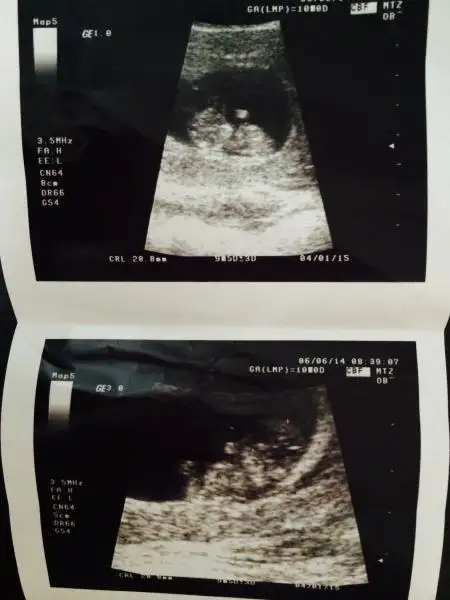

:34: bizim seninle aramızda 1 gün var. iki gün önceki ultrason görüntüsünü koydum. hala bişey diyen olmadı. ama benimkinde de çıkıntı net değil. bende tam anlayamadım. kız mı dedim kendi kendime. ama 1 oğlum var bu da kız olsun isterim yani, o yüzden mi kıza yoruyorum bilmiyorum. ama erkek nubu popoya paralel değil dik se eğer kız olma ihtimali daha yüksek bence. paralel net anlaşılmayabilir ama erkek anlaşılır bence, bu nub yöntemi aksi çıkan varmı bilmiyorumki

bak bu 2 gün önceki görüntü